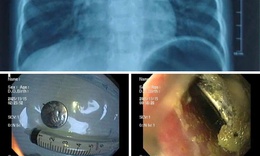

Nội soi gắp dị vật là vòng bạc trong dạ dày bé gái 5 tuổi

Y tế - 09/10/2025 18:30SKĐS - Mới đây, Bệnh viện Việt Nam – Thụy Điển Uông Bí tiếp nhận và xử trí thành công trường hợp trẻ 5 tuổi nuốt phải dị vật là chiếc vòng tay bằng bạc, dài khoảng 7 cm.